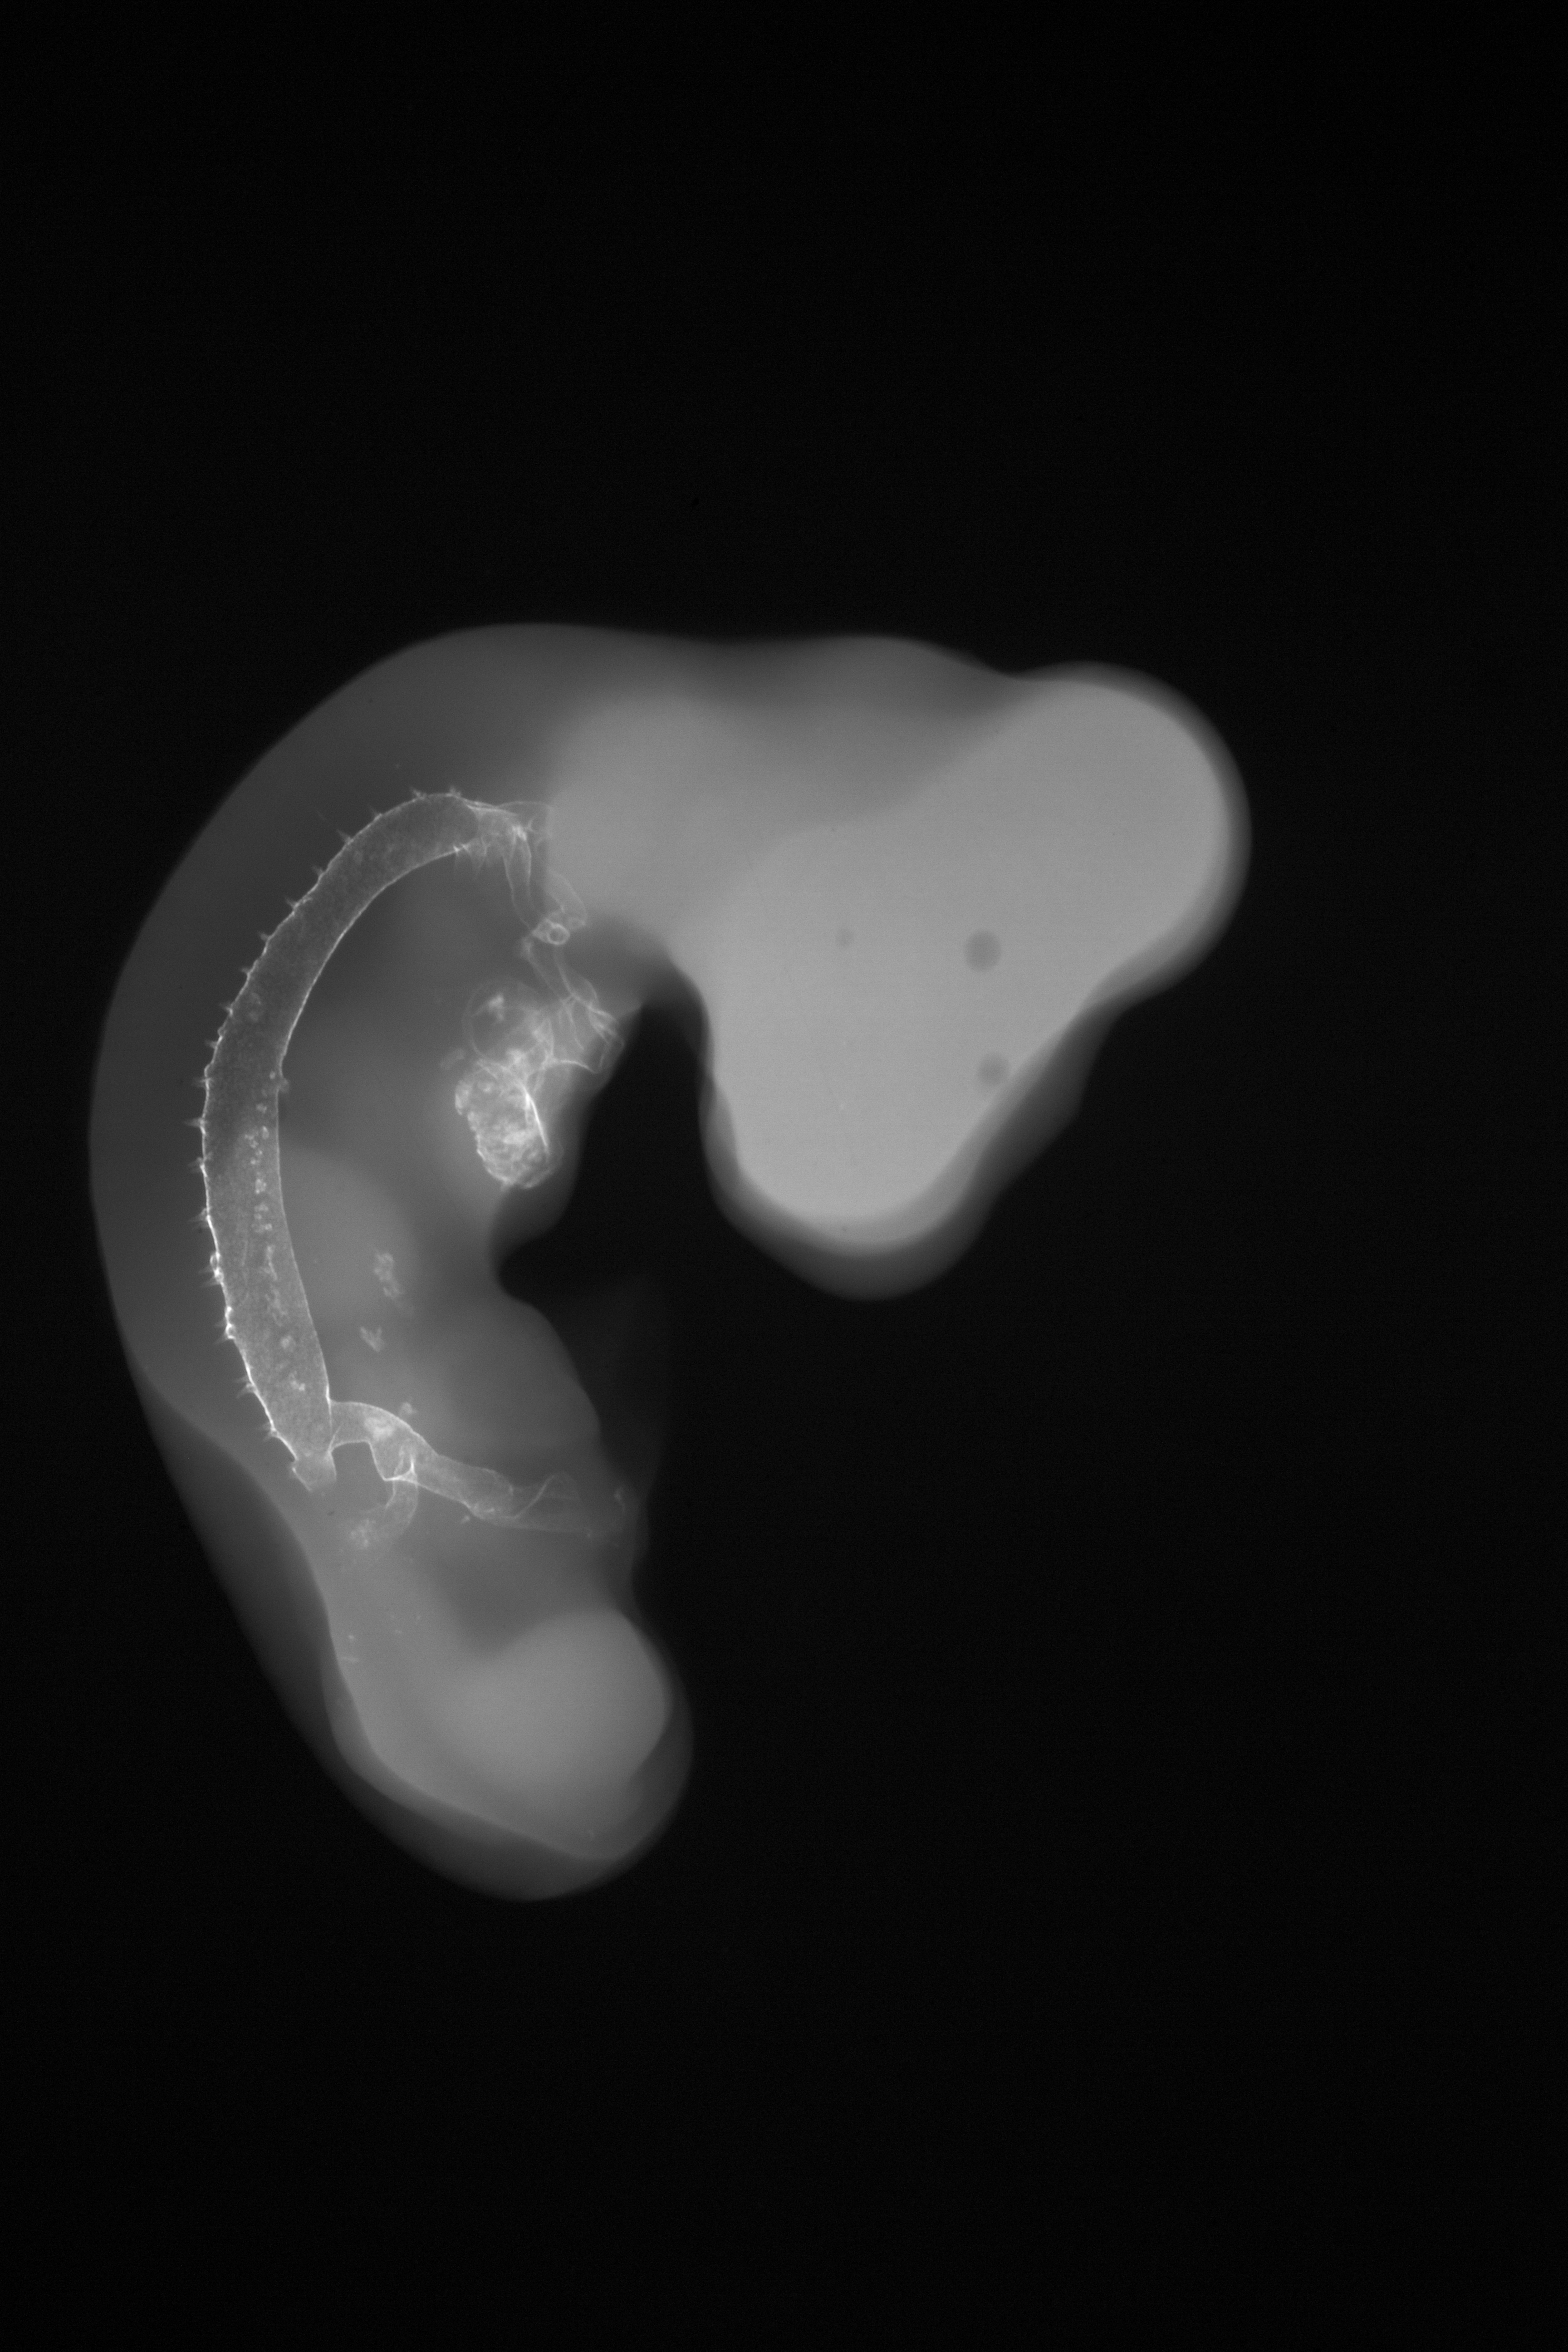

Chick Embryo Microangiography

Hamburger-Hamilton (HH) Stage 22 (approx. 4 days)

Stereo X-Ray Micrographs